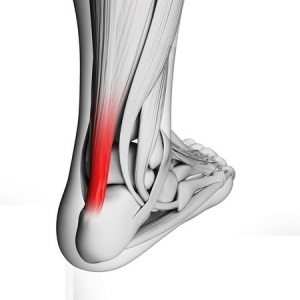

Achilles Tendonitis—this long tendon that runs down the back of your lower leg connects your calf muscle to the heel bone. It can be aggravated or injured from overuse such as someone whose job involves climbing a ladder. Athletes and “weekend warriors” who suddenly increase the intensity of their workout routine may also suffer from Achilles issues.

At Superior Foot & Ankle Care Center a condition that we frequently see in both experienced athlete’s and “weekend warriors” is Achilles tendonitis. The Achilles tendon, also known as the heel cord, is a band of tissue that runs down the back of your lower leg, connecting your calf muscle to your heel bone. Although it is the strongest tendon in the body, it is also one of the most frequently injured. Inflammation of the Achilles tendon, known as Achilles tendonitis is an overuse injury which is caused by putting too much stress on the tendon too abruptly. If left untreated, the ongoing stress to the tendon prevents the body from repairing the injured tissue and the result is a continued pain. Below are some strategies for avoiding this common podiatric disorder:

The day after a particularly intense workout or a long run you may notice pain ranging from mild to extreme in the lower part of the back of your leg. Or, you may be noticing a sluggish feeling in your leg accompanied by stiffness and/or a dull ache that lessens as you stretch the leg and get going with your day. All of these are possible symptoms of Achilles tendonitis—an inflammation of the large tendon that runs between the bottom of your calf muscle and your heel that we see often at Superior Foot & Ankle Center.